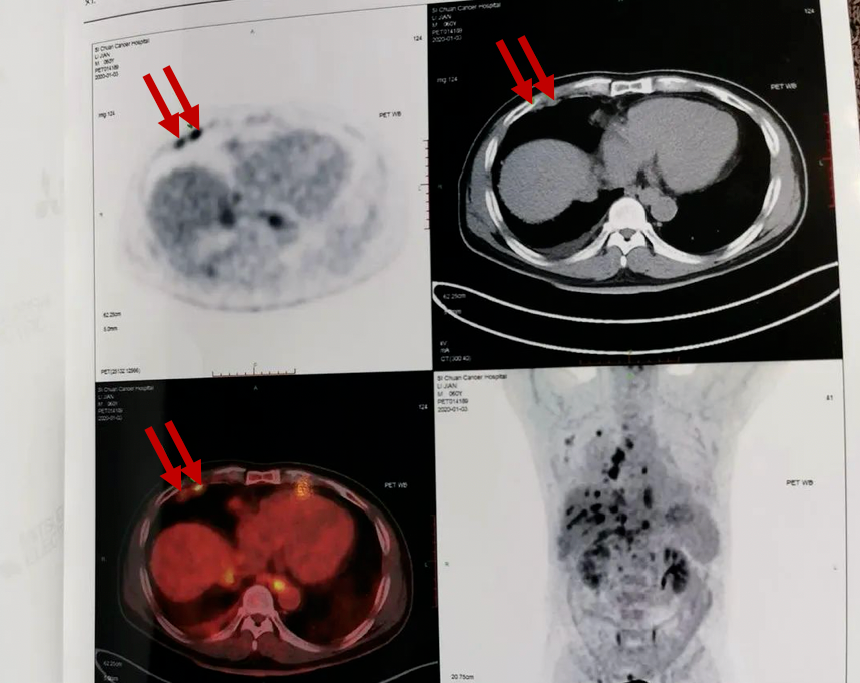

PET-CT成像清晰,并且还有立体图像。由于病灶部位可聚集大量示踪剂,而周围组织浓度比较低,在片子上会显示出比较明显的差异,在医生的指引下,普通老百姓也能大致看懂。让大家更能直观了解PET-CT片,了解自身的身体状况。

(下图箭头处可以看到患者右侧胸膜处明显的“亮点”,黑色的“放射性浓聚灶”,提示恶性肿瘤可能)